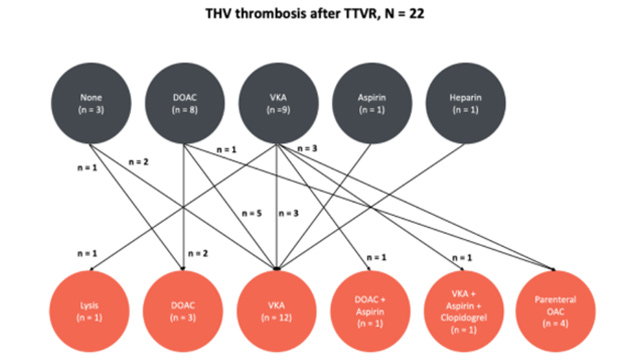

Featured research - Tricuspid valve intervention: the TRIPLACE registry

17 Nov 2025 – From PCR London Valves 2025

This session features cutting-edge research on tricuspid valve interventions, including insights from the TRIPLACE registry on orthotopic TTVR thrombosis, predictive value of three-dimensional tricuspid annulus measurements for procedural outcomes, early clinical experiences with novel TTVR systems, and procedural clipping strategies based on results from the BRIGHT...